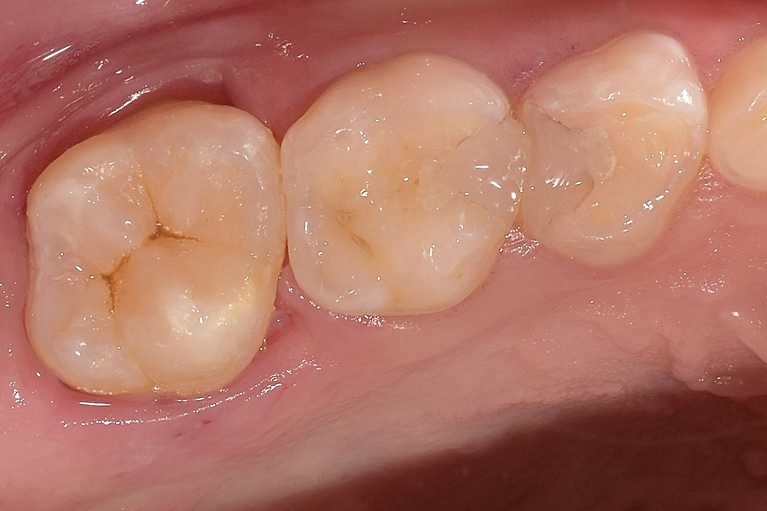

術後

| 治療名 | ダイレクトボンディング、MTAセメントを用いた歯髄保存 |

| 治療説明 | 歯髄に到達する大変大きな虫歯がありました。まだ若い患者であり、通常通り根管治療を行うと、歯質が薄くなり歯の寿命に大きく影響すると考えました。う蝕と感染の疑いがある歯髄を除去し,正常歯髄をMTAセメントを用いて保存した上で、ダイレクトボンディングにて歯の形を回復しました。 |

| 治療回数・期間 | 1回 |

| 副作用とリスク | 歯髄が感染し根管治療が必要となる可能性があります。レジンの着色、破折が起こり、研磨や再修復が必要となる可能性があります。 |

| 料金(税込) | MTAセメント:55,000円 ダイレクトボンディング:55,000円 |